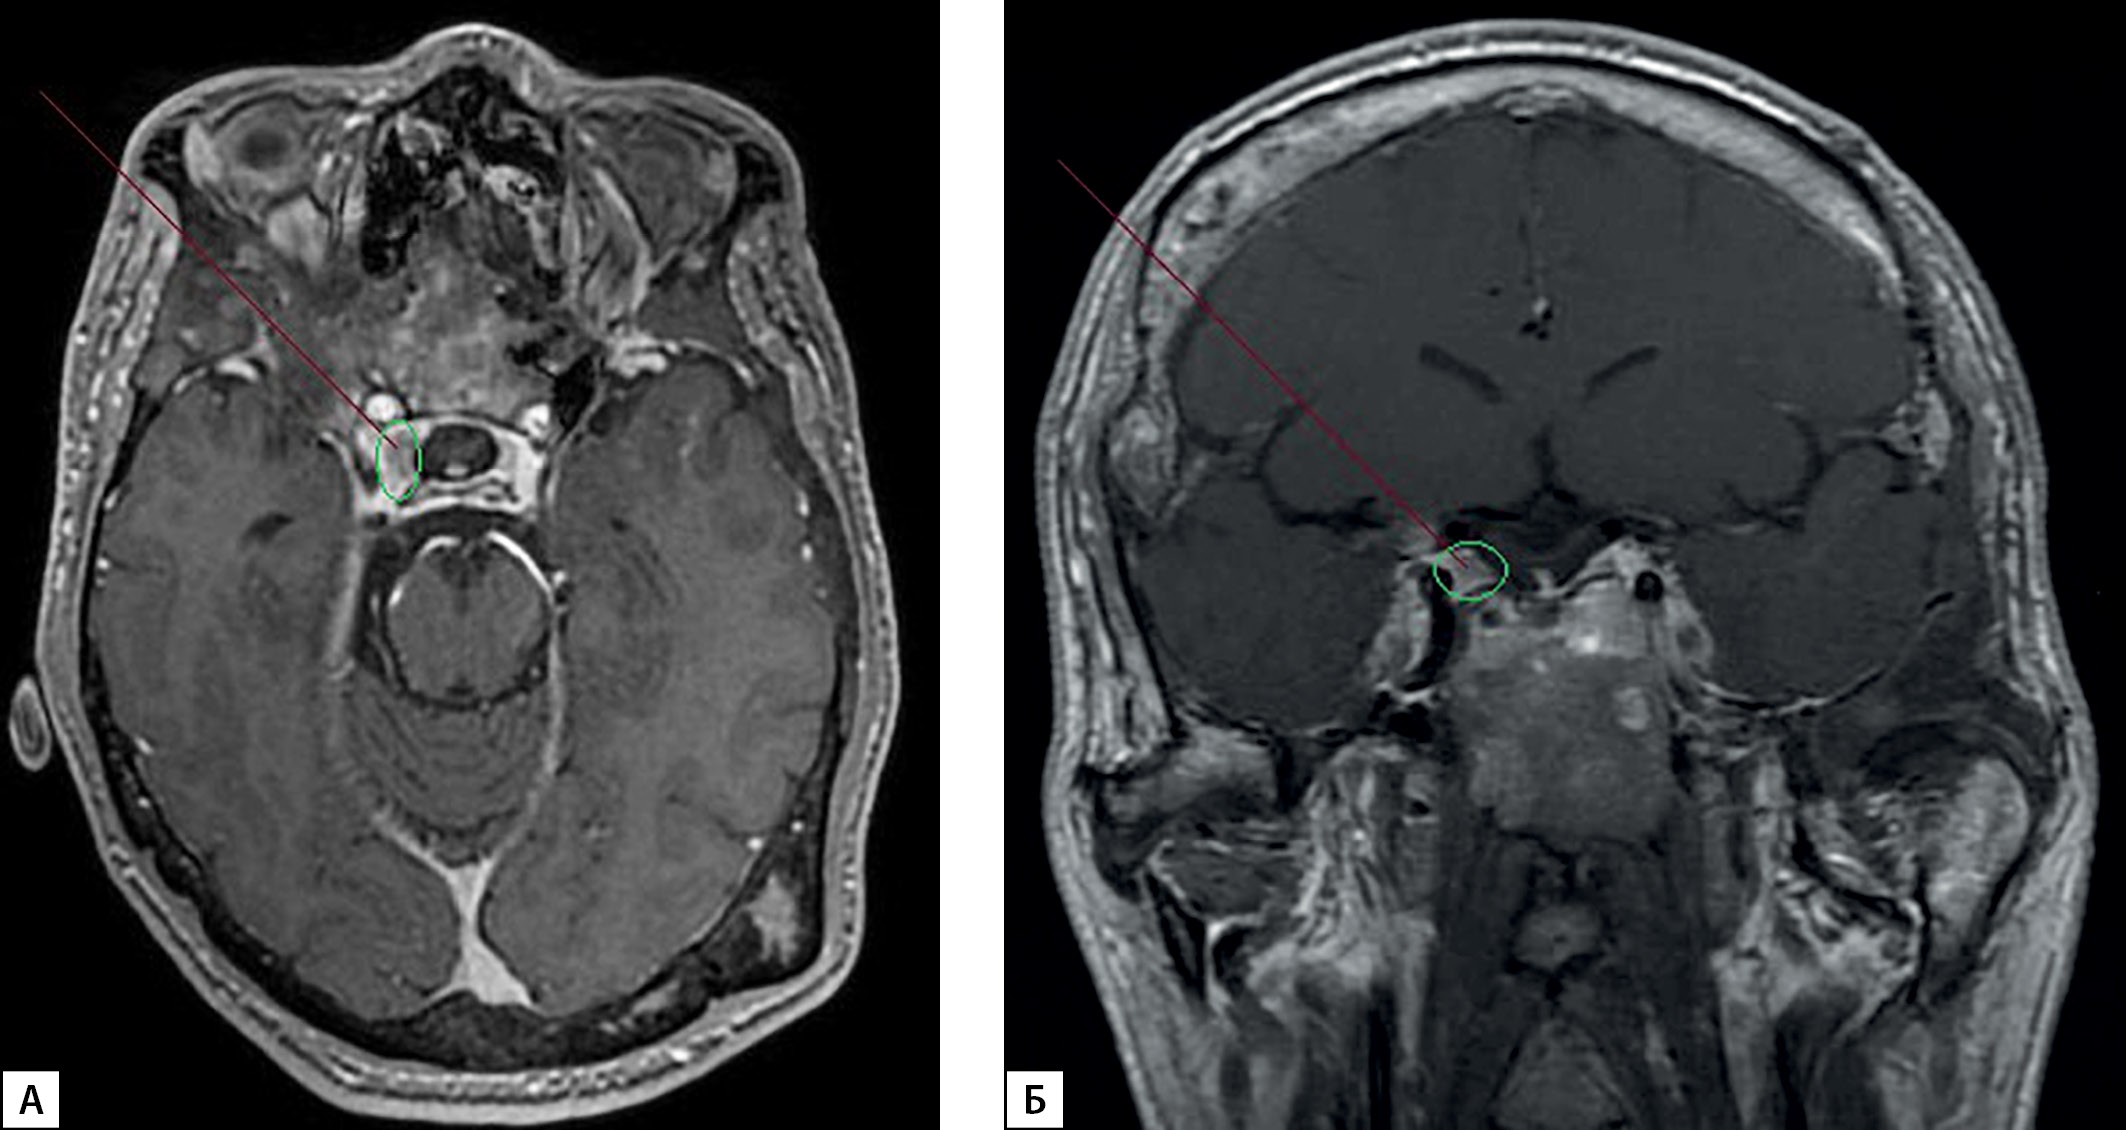

3. Figure 3. MRI of the brain of patient K. with McCune-Albright-Braitsev syndrome (contrast enhancement, December, 2021). | |

| Subject | ||

| Type | Исследовательские инструменты | |

View

(271KB)